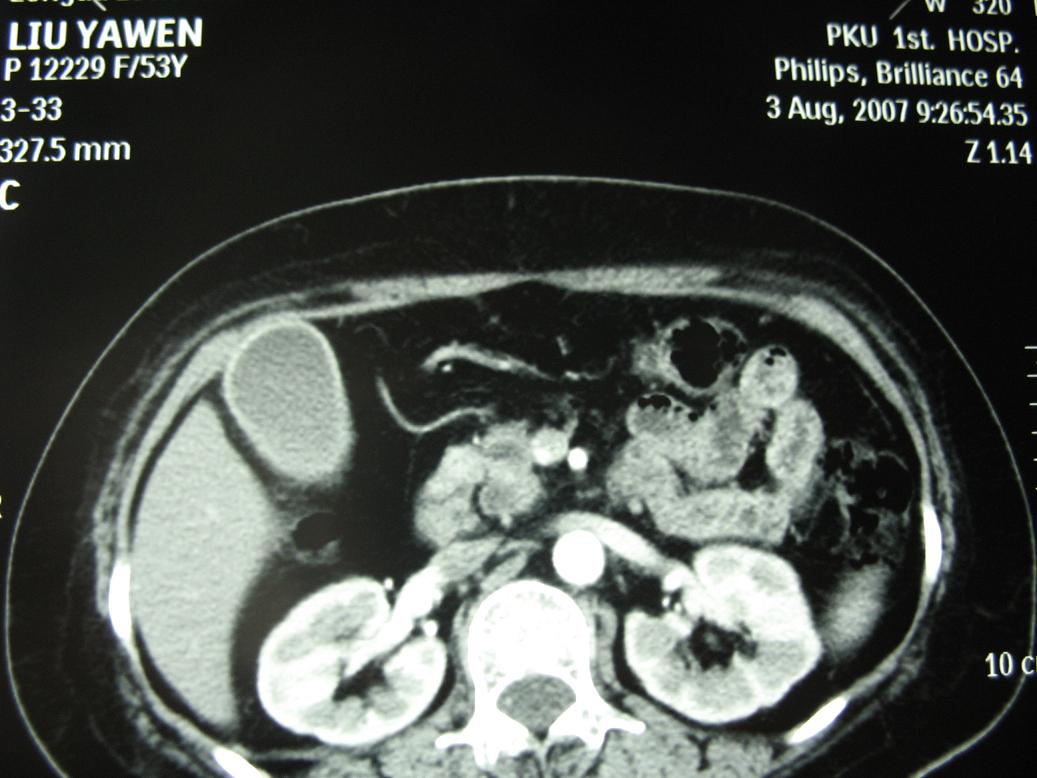

标题: CT17151:女 53岁 腹痛数月余 轻微黄疸 [打印本页]

女 53岁 腹痛数月余 轻微黄疸

1)考虑胰头癌。2)胆囊炎。

壶腹周围占位(钩突ca?)

胰腺钩突mt

支持胰腺钩突ca伴胆系梗阻,胆囊炎

考虑 胰头癌可能性大。